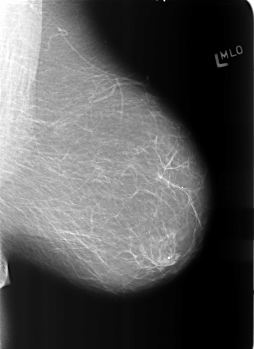

ics_version 1.0 filename B-3365-1 DATE_OF_STUDY 18 11 1997 PATIENT_AGE 41 FILM FILM_TYPE REGULAR DENSITY 1 DATE_DIGITIZED 13 7 1998 DIGITIZER LUMISYS LASER SEQUENCE LEFT_CC LINES 5632 PIXELS_PER_LINE 4032 BITS_PER_PIXEL 12 RESOLUTION 50 NON_OVERLAY LEFT_MLO LINES 5584 PIXELS_PER_LINE 4064 BITS_PER_PIXEL 12 RESOLUTION 50 NON_OVERLAY RIGHT_CC LINES 5744 PIXELS_PER_LINE 4008 BITS_PER_PIXEL 12 RESOLUTION 50 OVERLAY RIGHT_MLO LINES 5760 PIXELS_PER_LINE 4072 BITS_PER_PIXEL 12 RESOLUTION 50 OVERLAY |

FILE: B_3365_1.RIGHT_MLO.OVERLAY TOTAL_ABNORMALITIES 1 ABNORMALITY 1 LESION_TYPE CALCIFICATION TYPE PLEOMORPHIC DISTRIBUTION CLUSTERED LESION_TYPE MASS SHAPE IRREGULAR MARGINS ILL_DEFINED ASSESSMENT 4 SUBTLETY 4 PATHOLOGY BENIGN TOTAL_OUTLINES 1 BOUNDARY |

FILE: B_3365_1.RIGHT_CC.OVERLAY TOTAL_ABNORMALITIES 1 ABNORMALITY 1 LESION_TYPE CALCIFICATION TYPE PLEOMORPHIC DISTRIBUTION CLUSTERED LESION_TYPE MASS SHAPE IRREGULAR MARGINS ILL_DEFINED ASSESSMENT 4 SUBTLETY 4 PATHOLOGY BENIGN TOTAL_OUTLINES 1 BOUNDARY |